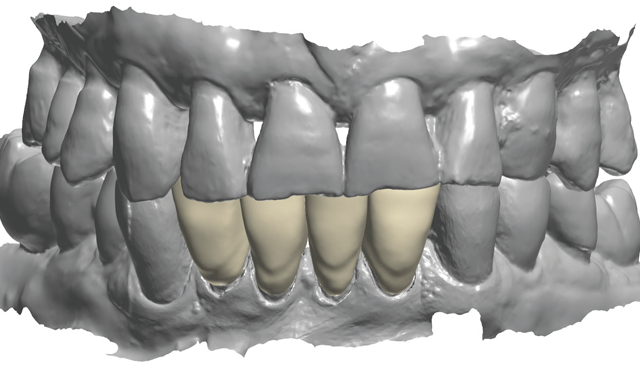

An 88-year-old man presented for restoration of tooth #25, which was fractured and had been endodontically treated (Fig. 1). A thorough intraoral and radiographic examination was performed, which revealed damage to the remaining anterior mandibular teeth incurred over the years as a result of scaling and curettage (Fig. 2). This damage to the

Treatment began by taking an intraoral 3D impression scan (3Shape TRIOS 3) (Fig. 4), after which a digital diagnostic “waxup” was created using Dental Designer (Fig. 5). Using digital intraoral scanning and digital “waxups” eliminated the need for time-consuming conventional impression taking, saving the patient time and eliminating discomfort. Additionally, proper shading, tooth size and contouring could be determined by examining and manipulating the digital impression/model images and

discussing the proposed changes with the patient.